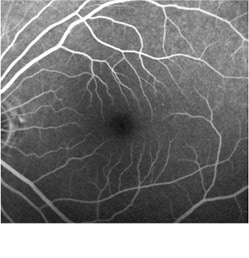

・蛍光眼底造影

蛍光色素の入った造影剤を腕の静脈から注射して、眼底カメラで眼底の血管を観察します。

血管の形や位置、血管からの血液中の水分のもれ具合などがわかります。

<正常>

蛍光眼底造影の図 正常

<病的近視における脈絡膜新生血管>